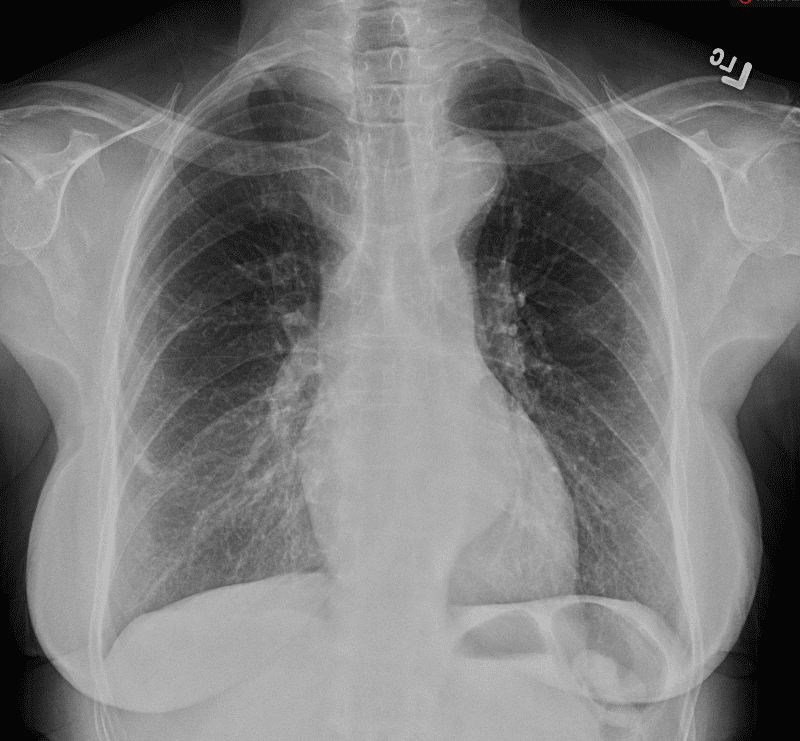

Practice Cases